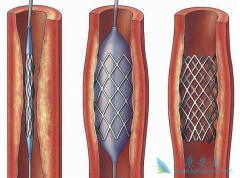

为了改善冠心病介入治疗短期和长期的疗效与安全性,所以研发了支架。第一代支架是金属裸支架,使冠心病介入治疗前进了一大步,使介入治疗变得非常安全,当血管发生严重狭窄时单纯球囊扩张预处理后,再用支架把血管完全撑开,就能解除心肌缺血危险,而且 ...

心脏支架 选哪种?放最好的支架?还是放最贵的支架?今天就给大家答疑解惑!心脏支架由具有强支撑力的合金制成,不同厂家支架的金属结构略有差别。心脏支架没有植入体内之前,包裹在球囊外面。植入时给球囊加压,支架打开至预定直径,使支架与血管壁完 ...

不少人都听过心脏支架手术,这种手术堪称是当代心脏病学最伟大的一项发明。你知道这个小小的支架是怎么放到心脏里去的吗? 心脏支架 是通过介入手术的方式植入到人体的,我们可以从心脏介入手术可是说起,这样更好理解。心脏介入原理其实并不复杂。 ...